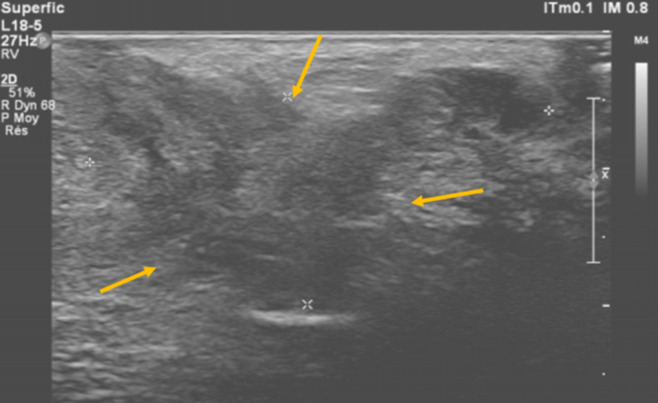

子宫内膜异位症是一种慢性非癌性妇科疾病,通常见于育龄妇女。它描述了子宫内膜腔外存在功能性子宫内膜成分、腺体和间质,最常涉及卵巢、腹膜和子宫韧带等盆腔结构。会阴子宫内膜异位症是一种罕见的盆腔外子宫内膜异位症,估计发病率在0.3%至1%之间。我们报告了一例36岁的孕妇,妊娠1段(G1P1),有阴道分娩史,没有子宫内膜异位症的病史,在接受会阴中外侧切开术两年后,出现了位于右侧会阴疤痕的疼痛肿块。肿块与周期性疼痛和生活质量明显受损有关。临床检查,结合超声和磁共振成像(MRI),建议在没有其他子宫内膜异位症病变的情况下诊断会阴子宫内膜异位症。由于患者拒绝手术,开始激素治疗,在8个月的随访中症状明显改善。虽然没有获得组织学证实,但典型的临床表现,令人回味的MRI特征以及对激素治疗的良好反应支持会阴子宫内膜异位症的诊断。在会阴切开术后出现周期性会阴疼痛的育龄妇女中,应系统地考虑这一未被充分认识的实体。

Endometriosis is a chronic, non-cancerous gynecological disorder that is typically observed in women of fertile age. It describes the presence of functional endometrial components, glands and stroma outside the endometrial cavity, most often involving pelvic structures such as the ovaries, peritoneum, and uterine ligaments. Perineal endometriosis is a rare form of extrapelvic endometriosis, with an estimated incidence of between 0.3% and 1%. We report the case of a 36-year-old woman, gravida 1 para 1(G1P1), with a history of vaginal delivery and no known history of endometriosis, who presented with a painful mass located on the right perineal scar two years after undergoing a mediolateral episiotomy. The mass was associated with cyclical pain and significantly impaired quality of life. Clinical examination, combined with ultrasound and Magnetic Resonance Imaging (MRI), suggested the diagnosis of perineal endometriosis in the absence of other endometriotic lesions. As the patient declined surgery, hormonal therapy was initiated, resulting in marked symptom improvement at 8-month follow-up. Although histological confirmation was not obtained, the typical clinical presentation, evocative MRI features, and favorable response to hormonal therapy supported the diagnosis of perineal endometriosis. This under-recognized entity should be systematically considered in women of reproductive age presenting with cyclical perineal pain following episiotomy.